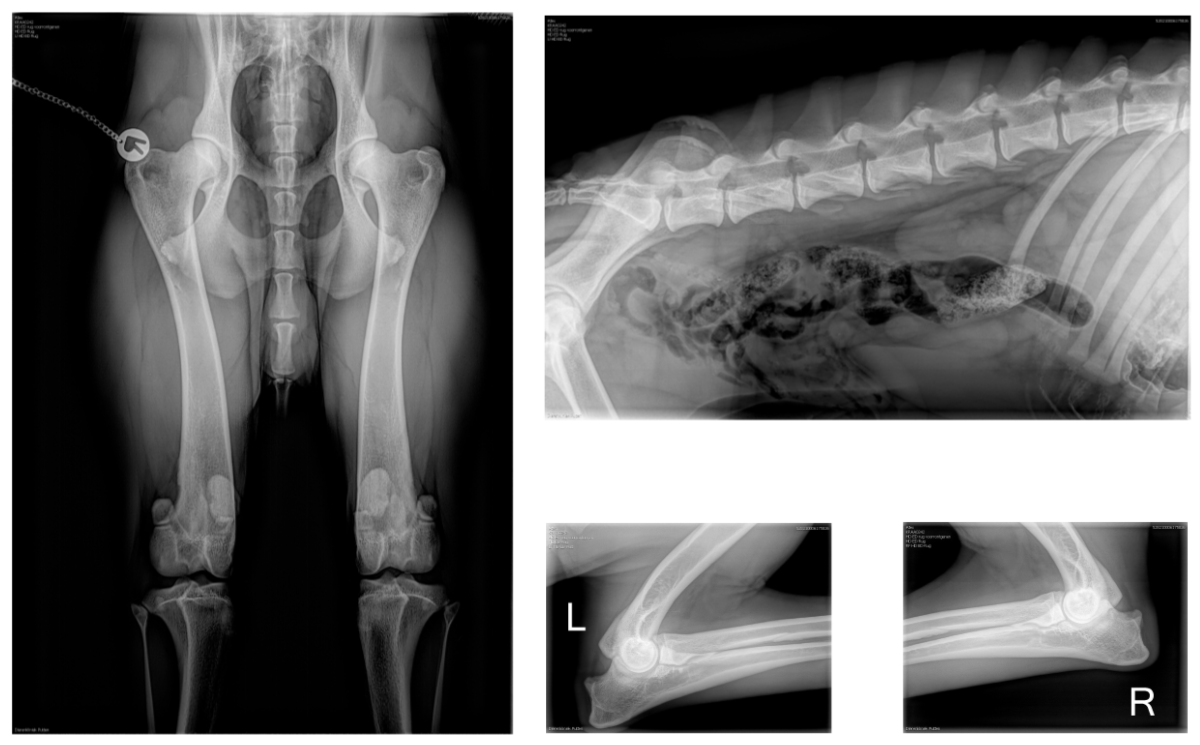

Dutch Racing Dog Thunderstruck "Atex"

1 march 2020 * 74 cm * 32 kg * Pedigree * HD/ED/Back * DNA & Heart tests * Race Results

HD A * Elbows 0/0 * Clear back * Spine L1 - L7 clear * knees checked => no PL, his knees are rock solid